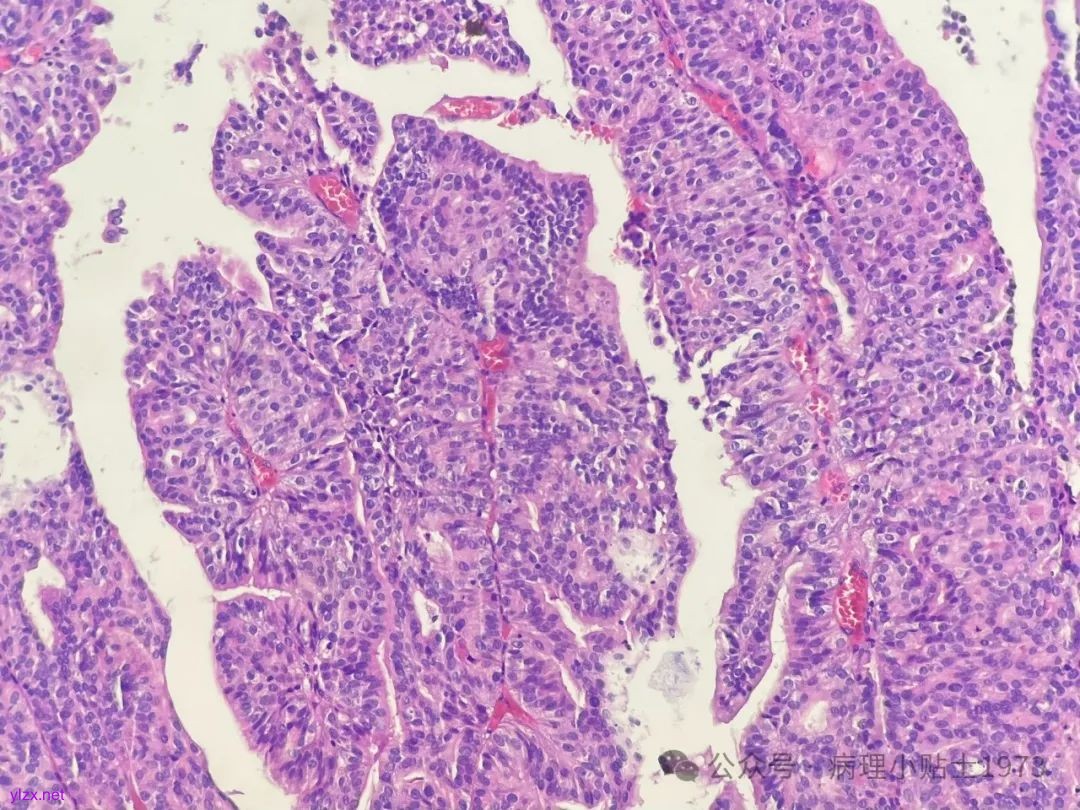

02 病例切片

诊断:非浸润性乳头状尿路上皮癌伴显著腺性分化

问题一:本病例出现了显著的腺性分化,不要误诊为单纯的腺癌。仔细寻找,仍然可以见到复层排列的经典尿路上皮癌成分。

问题二:本病例的肿瘤极性轻度紊乱,细胞核轻度到中度异型,部分可见清晰小核仁清晰,凋亡易见,免疫组化弥漫表达p16和CK20(弥漫阳性多见于高级别病变),ki67指数较高。到底该归入低级别还是高级别病变呢?